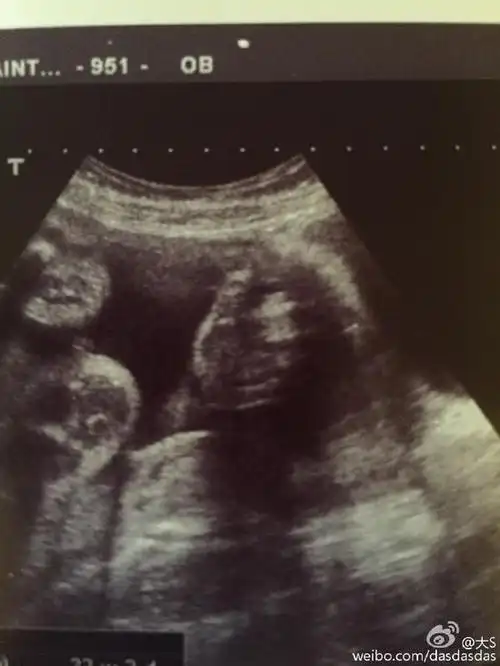

大s晒二胎儿子b超似点赞 称结婚五年不易